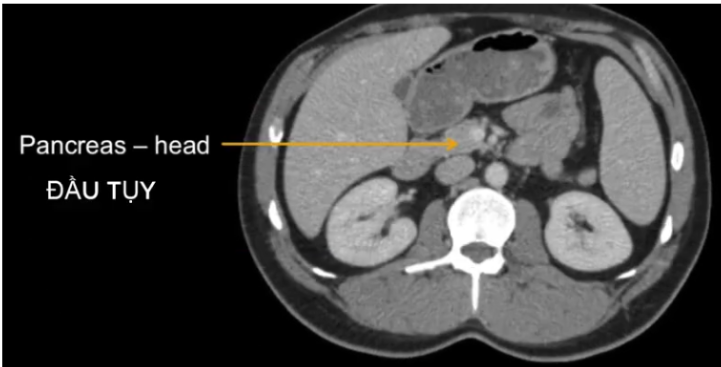

a) Túi mật TA viết là?